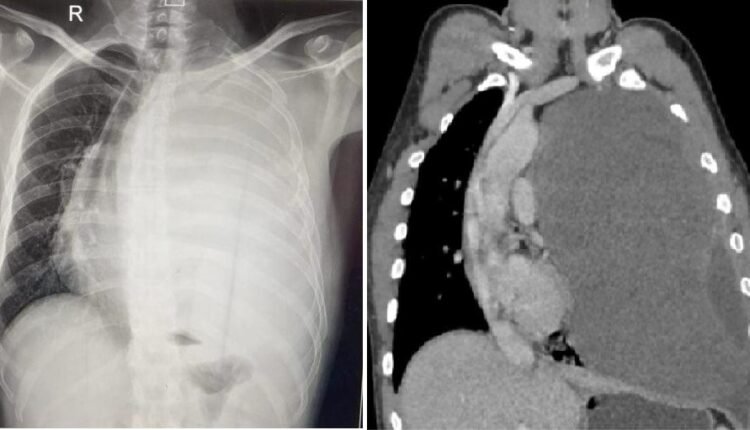

विक्रम सिंह को छाती में दर्द की समस्या जुलाई 2023 में शुरू हुई थी। लगभग एक साल से वह छाती में होने वाले तीब्र दर्द से परेशान थे। आस-पास के अस्पतालों से लेकर उन्होंने राज्य के अन्य बड़े अस्पतालों में भी अपनी बीमारी का परीक्षण कराया। थोरेसिक सर्जन उपलब्ध नहीं होने की वजह से जब कई अस्पतालों ने हाथ खड़े कर दिए तो विक्रम की अन्तिम उम्मीद ऋषिकेश एम्स पर आकर टिक गई। पिछले महीने एम्स पहुंचने पर विक्रम ने सीटीवीएस विभाग के चिकित्सकों को अपनी समस्या से अवगत कराया। सीटी स्कैन कराने पर डॉक्टरों ने जब रिपोर्ट देखी तो पता चला कि मरीज के बाएं फेफड़े पर एक विशालकाय ट्यूमर बन गया है, जो उस फेफड़े को पूरी तरह दबाने के साथ-साथ कभी भी दाएं फेफड़े को भी अपनी चपेट में ले सकता था।

एम्स के हृदय छाती एवं रक्त-वाहिनी शल्य चिकित्सा (सी.टी.वी.एस.) विभागाध्यक्ष डॉ. अंशुमान दरबारी ने बताया कि हाई रिस्क में होने के बाद भी ट्यूमर निकालने के लिए ओपन सर्जरी करने का निर्णय लिया गया। डॉ. दरबारी ने बताया कि बीती 11 जून को उनकी कुशल टीम ने सर्जरी द्वारा मरीज की छाती खोलकर एक ही बार में पूरा ट्यूमर निकाल दिया। सर्जरी करने वाली टीम में डॉक्टर दरबारी के अलावा सीटीवीएस विभाग के डॉक्टर अविनाश प्रकाश और एनेस्थेसिया विभाग के डॉ. अजय कुमार का विशेष योगदान रहा। ग्रसित मरीज की छाती से निकाला गया ट्यूमर 22×20 सेमी. और 3.2 किलोग्राम वजन का है।